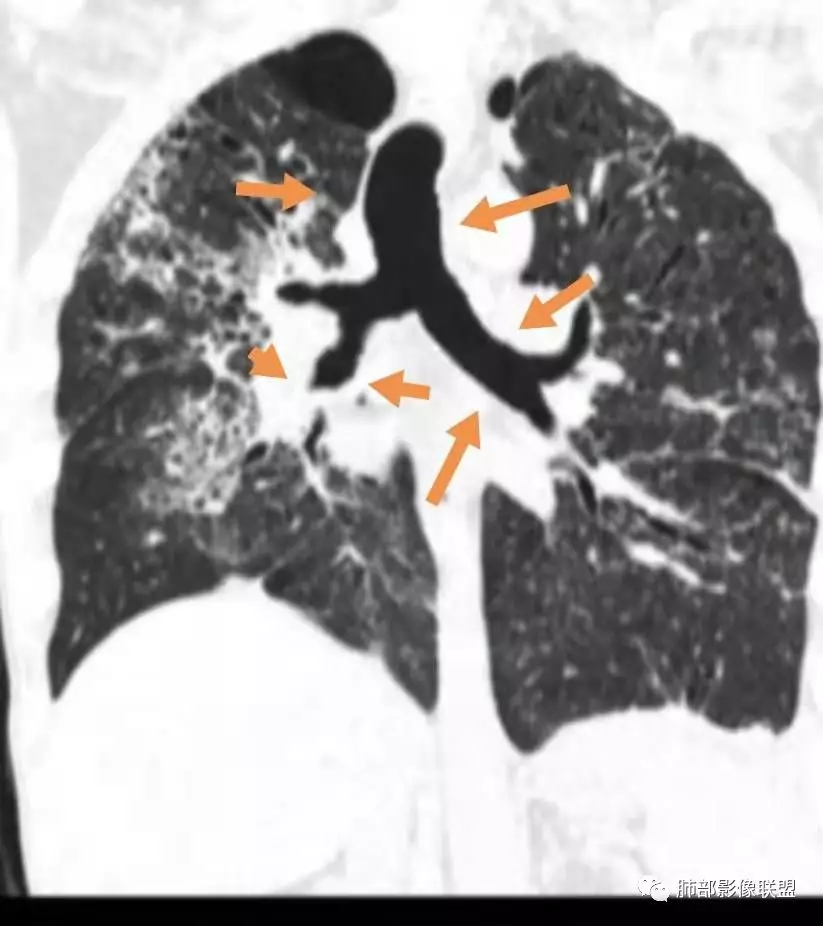

双肺间质性病变,中央间质增厚,胸膜下间质增厚,左侧胸膜肥厚,胸廓变小,肋间隙变窄。

对,大的支气管血管周围

胸部CT:两肺弥漫病灶,磨玻璃影,少许实变,部分累及胸膜,磨玻璃区可见囊?少许胸腔积液,两肺可见结节,支气管血管束增粗,小叶间隔增厚,支气管走形有扭曲扩张,可见纤维化。气肿、大泡。考虑:感染性病变,PCP?查下HIV,CD4,G等。鉴别结核、结缔组织病肺浸润。

患者双上肺弥漫性改变,小叶间隔增厚,中央轴为主,胸膜下少量,感染为主,鉴别结核。

55多男性,发热为主诉,体温38℃-39℃多,午后及夜间发热为主,峰值40℃,伴黄痰,CRP高,血糖正常,胸部CT:两肺弥漫病灶,磨玻璃影,少许实变,部分累及胸膜,两肺可见结节,似可见树芽,支气管血管束增粗,小叶间隔增厚,见肺气肿、大泡。考虑感染性病娈,肺结核可能性大。

双肺弥漫性病变,多发磨玻璃密度及小叶间隔增厚,大部分沿支气管血管束分布,伴支气管轻度扩张,以午后及晚上发热为主,考虑感染性病变,间质性结核可能大,另双肺多发肺气囊,LIP待排

中年男性,发热为主诉,中低热,午后为主,hsCRP高,白细胞不高,胸部CT:两肺弥漫病灶,间质受累,以上和背为主,支气管有扩张有狭窄,对称性斑片、斑点,有播散灶,考虑特殊感染性疾病:结核。鉴别诊断淋巴瘤、OP。建议完善病学学及tspot,tblb。

中年男性,反复发热月余,crp很高,无糖尿病史。双肺上中肺野多发斑片磨玻璃影,沿支气管血管束分布,小支气管壁增粗,扩张,有树芽征,考虑肺结核,结节病待排。

病变一般沿血管支气管束分布或小叶分布,一般上肺多于下肺(这与常见继发性肺结核分布相若)。

常会伴有其他继发性肺结核病灶,如斑片影、结节影,树芽征,新旧不等改变。

2. 肺气肿背景(小叶中心性肺气肿);双肺多发病灶整体沿血管支气管束及胸膜下分布,以上叶及下叶背段分布为主,有实变及GGO,边界清楚,有树芽,小叶间隔及中央间质增厚,叶间裂见到多发结节,部分支气管不规则牵拉扩张,提示病灶纤维化明显,结合临床病史,考虑病灶为间质性感染,肺门及纵隔内有钙化淋巴结,小叶间隔结节,考虑淋巴道增值性疾病可能,综合常规要怀疑间质性肺结核。